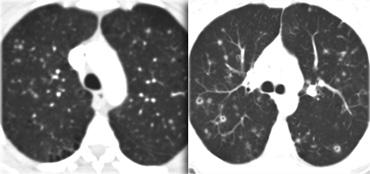

Dưới đây là hai ví dụ về viêm phổi quá mẫn bán cấp.

Có thể thấy các nốt trung tâm tiểu thùy bờ không rõ dạng kính mờ.

Đây là một trường hợp khác của viêm phổi quá mẫn bán cấp.

Có thể thấy hình mờ mờ nhạt ở trung tâm các tiểu thùy thứ cấp (mũi tên) với vùng dưới màng phổi được bảo tồn.

Hình ảnh HRCT này cũng cho thấy hình mờ trung tâm tiểu thùy mờ nhạt ở bệnh nhân HP bán cấp.

Lưu ý ranh giới không rõ của các nốt trung tâm tiểu thùy này.

Đôi khi các hình mờ trung tâm tiểu thùy có hình thái dạng nốt rõ hơn như trong trường hợp này.

Đây là một trường hợp khác của viêm phổi quá mẫn.

Có hình ảnh khảm.

Một số tiểu thùy thứ cấp biểu hiện kính mờ do thâm nhiễm phổi, trong khi các tiểu thùy khác sáng hơn do viêm tiểu phế quản với bẫy khí.

Bệnh nhân này nhập viện với triệu chứng khó thở cấp tính và phim X-quang ngực bình thường (không trình bày).

HRCT lúc nhập viện (trái) cho thấy các vùng kính mờ theo phân bố tiểu thùy.

HRCT kiểm tra mười ngày sau (phải) cho thấy các tổn thương đã thoái lui hoàn toàn mà không cần điều trị.

Các tổn thương được cho là do viêm phổi quá mẫn.